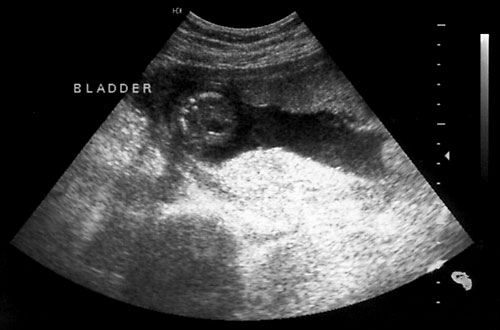

- Bladder

Normal fetal bladder at 18 weeks (left, at arrow). Lovely picture of both uterine arteries around normal bladder (right). This color flow picture documents the presence of the 3 vessel cord with the demonstration of the two uterine arteries coursing around the bladder. - Spine (need two perpendicular views)